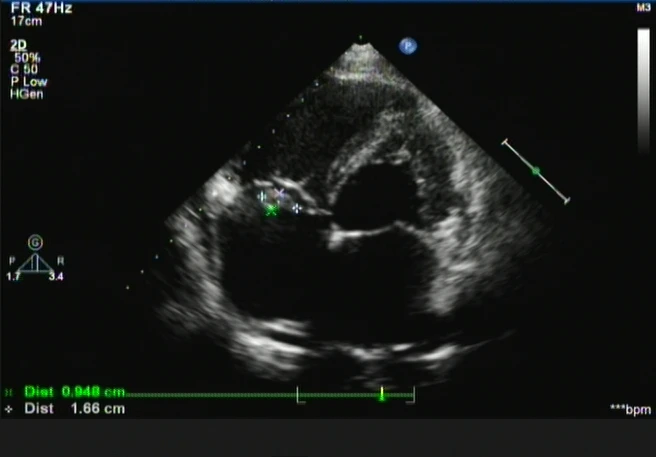

这天上午,超声心动图室来了一位24岁的年轻患者,主诉既往体健康但胸闷半月余,我看着体型微胖的小伙,心中暗忖“会不会是精神压力过大而导致的短时间身体不适感呢?”,一套常规流程下来,我的初步印象:双房增大,双室轻大;右房中等回声团,占位?(图1)三尖瓣中量偏心性花色湍流(图2)。

图1 图2